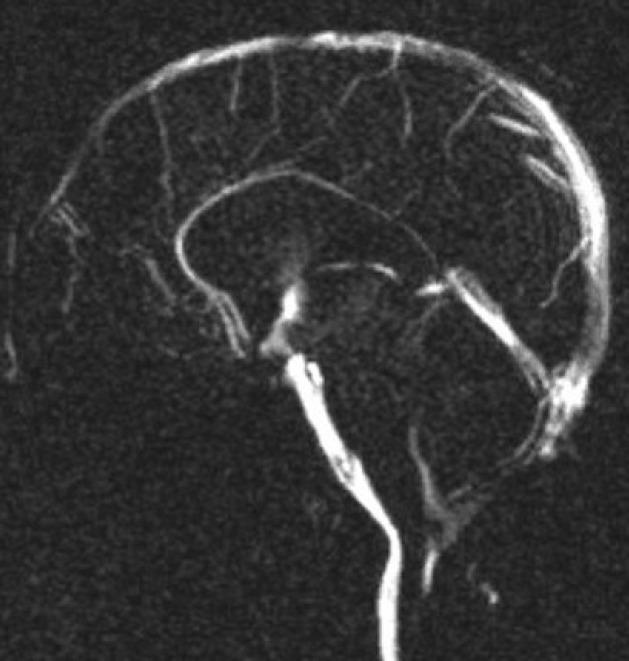

Endoscopic third ventriculostomy (ETV) has now become an accepted mode of hydrocephalus treatment in children. Varying degrees of success for the procedure have been reported depending on the type and etiology of hydrocephalus, age of the patient and certain technical parameters. Review of these factors for predictability of success, complications and validation of success score is presented.

内镜下第三脑室造瘘术(ETV)现已成为治疗儿童脑积水的一种公认方式。根据脑积水的类型和病因、患者年龄以及某些技术参数,该手术已报道有不同程度的成功率。本文对这些因素进行综述,以探讨其对手术成功率的预测性、并发症以及成功评分的验证情况。